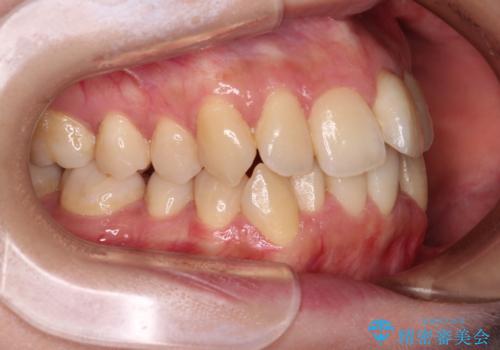

1. 【モニター】急速拡大装置 狭い歯列を拡大してワイヤー装置で短期間治療の治療前